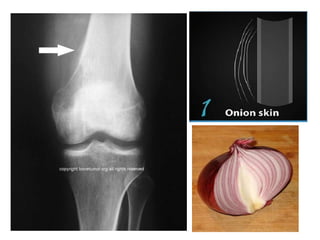

Plain Radiography

• Presents as extensive diaphyseal lesion

• At midshaft of the long bone, the cortex

displays increased density, extending

externally as periosteal new bone, forming

multiple thin parallel layers giving ‘onion peel

appearence’

• Periosteal reactions may also have codmans

triangle- lifting of periosteum from the bone.

• Ewing sarcoma appears as ill defined, permeative,

focally moth eaten, destructive intramedullary

lesion accompanied by a periosteal

reaction(onion skin)

• Lesion may have both lytic and sclerotic regions

• Extraosseous component is radiolucent with the

same density of soft tissue.